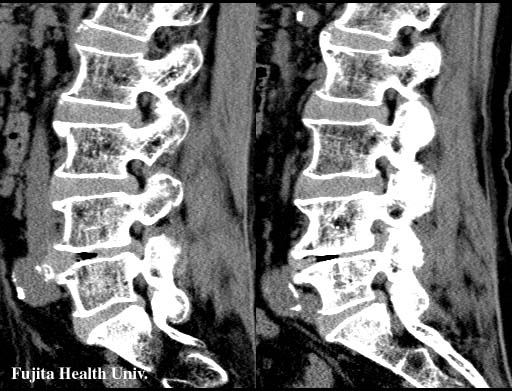

Lumber disc hernia

0.5mmx4, Pitch 3, 60-seconds, 135kV, 130-mAs:

Right and left parasagittal MPR

Stenosis of left L4/L5 intervertebral foramen by the soft disk is clearly visualized.